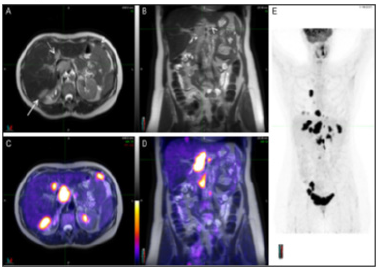

Molecular imaging: (Figure 8A, B) is defined as the ability to visualize and quantitatively measure the function of biological and cellular processes in vivo and has enormous relevance for patient care: it reveals the clinical biology of the disease process and has the potential to personalize a patient’s care. PPM and molecular imaging will enable us to accelerate and improve cancer management in future medicine. Thanks to the combination of several imaging modalities in the form of the multimodal Molecular Imaging (MI) strategy, a great advance has been made in early diagnosis, in more targeted and personalized therapy, and in the prediction of the results that will be obtained once the anticancer treatment is applied (Figure 9A, B).

Figure 9A:A typical representative of the PET/MRI molecular imaging benefits in PPM-related PPO cancer care. Staging PET/MRI scan of a 56-year-old woman with ovarian cancer. The MRI images (A and B) show multiple lesions abutting the liver posteriorly (long arrow), involving the porta hepatis (short arrow) and seeding the peritoneum (arrowheads). A round, well defined lesion with same features is also visualized in segment IV of the liver (dotted arrow). On PET/MRI images (C and D) the lesions earlier described, and others not so evident, are depicted by high FDG uptake confirming their malignant nature. Maximum intensity projection of the whole body (E) reveals several lesions both in the chest and abdomen.

The main purpose of imaging in oncology is pre-early and/ or subclinical detection to enable interception if not prevention of full-blown disease, such as the appearance of metastases. Molecular imaging - particularly when combined with liquid biopsy for screening purposes - promises especially early localization of disease for optimum management.

Advances in multimodality imaging, integrating anatomical and functional features of tumors, have allowed guiding clinicians in a prompt decision of the effectiveness of treatments in individual patients, thus reducing therapeutic failures. Indeed, molecular imaging methods allowing in vivo characterization and measurement of biological processes at the cellular and molecular level can detect mechanisms of drug resistance and avoid the use of an ineffective treatment in nonresponding patients. In addition, this approach can identify specific molecular targets, allowing the selection of patients for novel therapies [9].